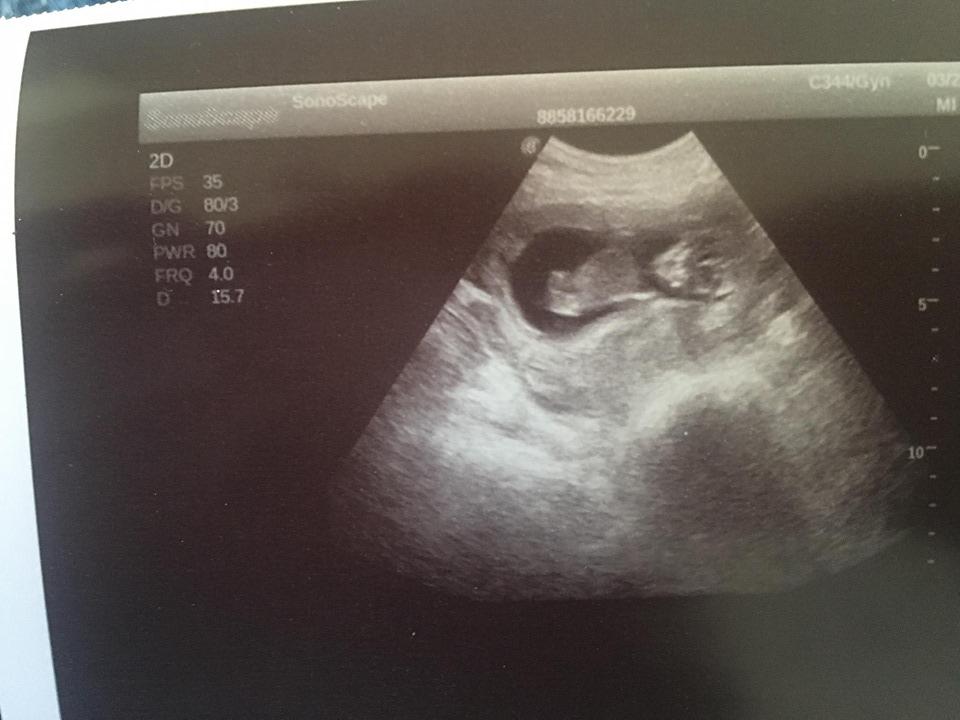

Je to holčička nebo chlapeček? Foto ultrazvuku

@juliemichal škoda, že ta fotka je rozmazana. Ale vypadá to spíš na kluka, opravdu tam něco trčí, ale na tento týden by to byl tedy už poradny chlapak 😃 až půjdete v tom 15+4, poproste o fotku pohlaví ze spodu, to už by mělo být pohlaví poznat.

@kajda3 no to je fakt na 12+1 by to byl pořádný chlapák hah,takže to co tam trčí to určitě nebude šula 😀 😀 ale uvidíme ♥ ♥ určitě v úterý poprosím dr aby mi dala fotečku pohlaví ♥ ♥

@sebinka123 kéž by ta první fotka (screening) podle dr to vypadá na kluka,druhá fotka 2 dny později u mého gynekologa ten mi řekl,že mezi nožičky nic nevidí,že by ho zajímalo kde doktor viděl chlapečka 😀 😀 ale,že z největší pravděpodobností mi pohlaví řekne až ve 20tt

@juliemichal to jsem na tebe zvedava! 😁 musíš nám dat v úterý hnedka vědět. První fotka bych řekla na 99% kluk, ale ta druha zase vypadá na holčičku. Moc bych ti tu holčičku prala 🙂

@eiram7 jasná holčička, gratuluji 💃ve 13. týdnu je to jisté tak na 95 % 😊 navíc k tomu tento snímek hrbolek ukazuje pěkně 👍